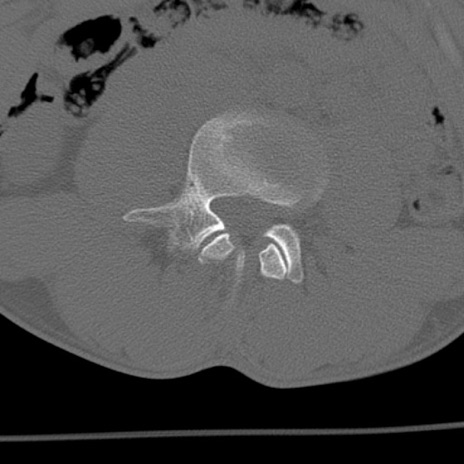

症例3 腰椎CT(横断像)

腰椎CT